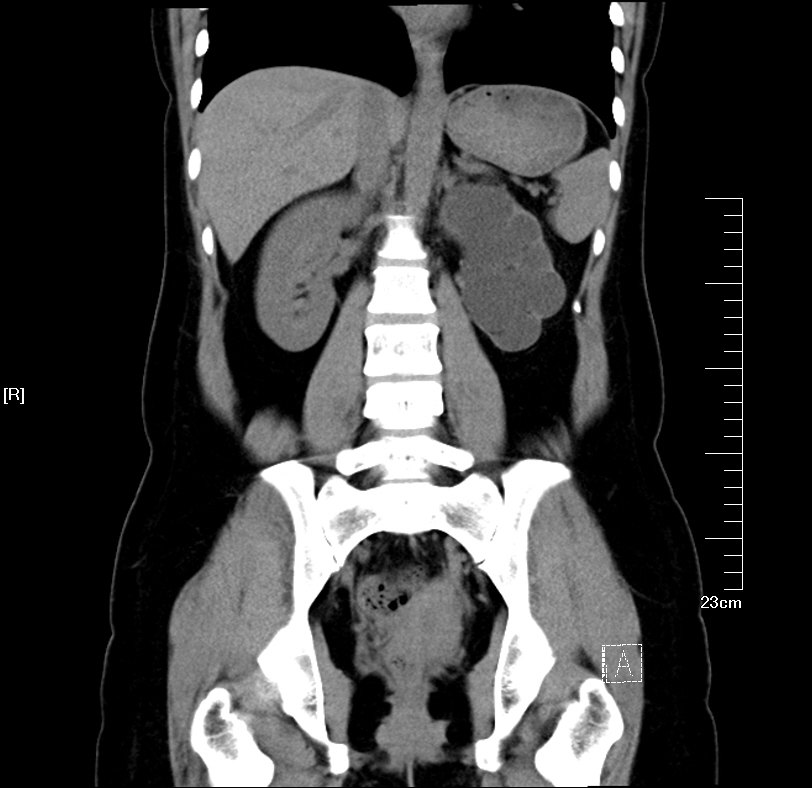

CT检查提示:双侧肾脏重度积水双侧输尿管中段结石 双侧输尿管上段积水扩张

2016年02月手术患者,男性,47岁,河北人,农民,主诉双侧腰部酸胀一年余,伴尿少三天;五年前曾因输尿管结石在当地予以震波碎石3次,后疼痛缓解后未重视,五年来未予以复查,三天前出现尿少,腰部酸胀加重与当地医院就诊后发现病情危重遂来我院求诊,CT:双侧肾脏重度积水,皮质菲薄,双侧输尿管上段扩张明显,双侧输尿管中段结石,左侧结石约1.7cm,右侧约2.8cm左右,GFR:左侧11.7ml/min,右侧16.1ml/min。肾功能:Cr 516umol/L;术前诊断:双侧输尿管结石 双肾重度积水 肾功能失代偿;行双侧经皮肾穿刺造瘘术,保护肾功能,十天后Cr下降至236umol/L,方行双侧输尿管镜检,但由于输尿管梗阻时间太长,输尿管迂曲扩张明显,中段输尿管与周围脏器严重黏连,输尿管镜无法顺利上行,遂行双侧输尿管切开取石术+双侧输尿管裁剪成型术。